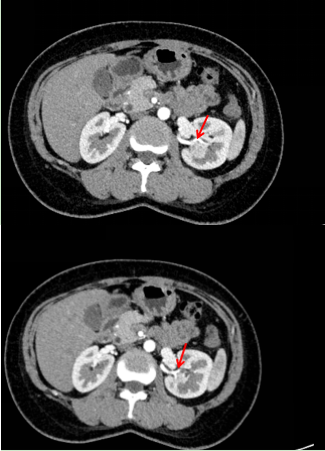

浦主任认真查看了李女士的CT图像:肿瘤大小约3.5*3.5*3.3cm,并不算大。然而肿瘤的位置较深,大部分埋于肾脏内,靠近肾盂和肾动脉,特别是肿瘤的上极紧贴两支肾动脉的分支。手术过程中一旦损伤动脉,很可能无法保留左肾,甚至可能引起大出血,危及生命。然而,直接进行左肾切除对于年轻的患者来说非常可惜。浦主任决定先将李女士收住入院,完善术前检查的同时组织科室内讨论,力争为患者制定安全可靠的保肾手术方案!

李女士入院以后,医生详细了解了她的病史。检查显示李女士的双侧肾脏功能良好,如果保肾手术成功,患者的获益很大。然而李女士体内肾肿瘤的RENAL评分为9分,RENAL评分越低则保肾的可能性越高,国际上认为RENAL评分>7分的患者更倾向于行根治性肾全切术。因此,浦金贤主任组织了科室内会诊,与多位主任一起对手术方案和步骤反复论证,充分预估手术过程中可能发生的意外情况,积极完善术前准备,也和患者及其家属进行了有效的沟通。

肿瘤上极毗邻肾动脉的两个分支